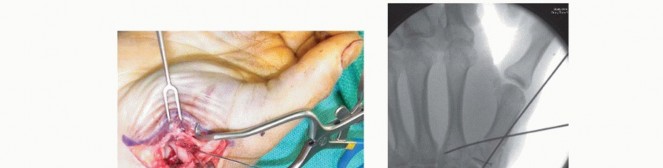

Closed Reduction and Percutaneous Pinning (CRPP)

CRPP is the treatment of choice for classic Bennett fractures where the volar-ulnar fragment is too small to reliably accept a lag screw, yet the joint can be anatomically reduced closed. The reduction maneuver is highly specific, designed to counteract the deforming forces of the APL and Adductor Pollicis. Longitudinal traction is applied to the thumb, followed by palmar abduction and pronation. Direct pressure is then applied to the dorsal-radial aspect of the metacarpal base, effectively pushing the shaft back into the anatomic cradle of the intact volar-ulnar fragment.

Once anatomic reduction is confirmed via multi-planar fluoroscopy, percutaneous fixation is achieved. Typically, two 0.045-inch or 0.062-inch Kirschner wires are utilized. The first wire is driven from the dorsal-radial aspect of the metacarpal shaft directly into the trapezium, effectively neutralizing the proximal pull of the APL. A second wire is often placed transversely from the first metacarpal shaft into the second metacarpal to control rotation and maintain the web space. Pins are cut outside the skin and capped to facilitate easy removal in the clinic.

Image